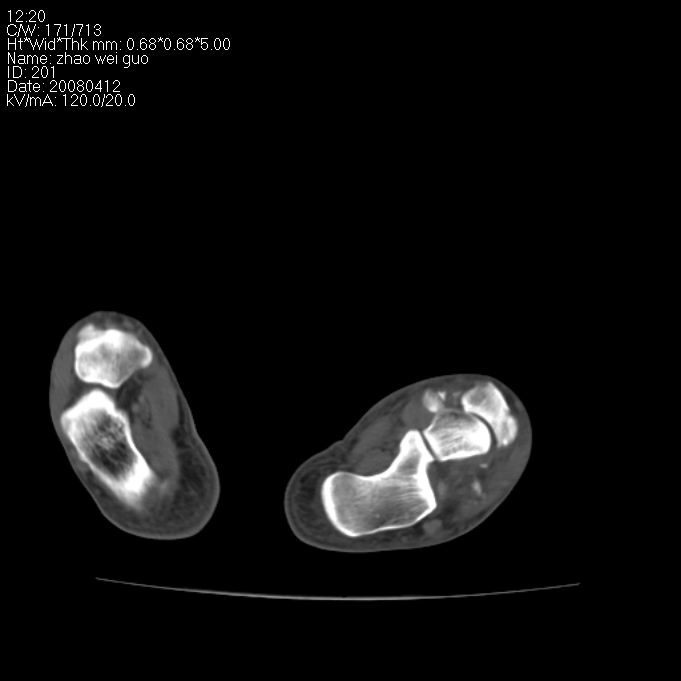

标题: CT12802:男 29岁 踝关节外伤 [打印本页]

标题: CT12802:男 29岁 踝关节外伤

看起来有点乱,不如平片好看,柘跖骨粉碎性骨折。

左侧跖附骨多发骨折

(左?)侧跖附骨多发性骨折。

左侧跖跗骨多发骨折.请结合平片进一步定位。

左侧跖附骨多发骨折。

左侧跗跖骨多发骨折

左侧跖附骨多发骨折,平片完全可以解决;没有必要。